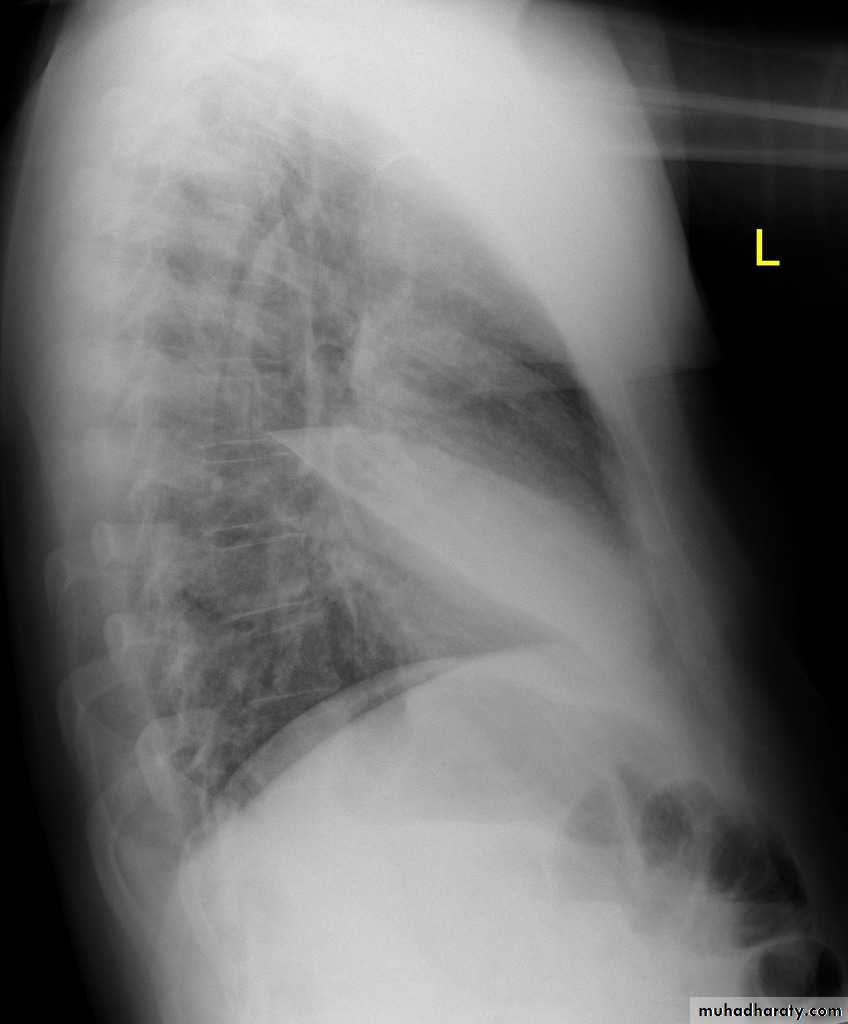

On lateral projections the left lower lobe is hyperexpanded and the oblique fissure displaced anteriorly. There is associated increase in the retrosternal opacity.

Left lower lobe collapse has distinctive features, and can be readily identified on frontal chest radiographs, provided attention is paid to the normal cardiomediastinal contours. The shadow cast by the heart does however make it harder to see than the right lower lobe collapse

Radiographic features

Left lower lobe collapseis readily identified in a well penetrated film of a patient with normal sized heart, but can be challenging in the typical patient with collapse, namely unwell patients, with portable (AP) often under-penetrated films, often with concomitant cardiomegaly. Features to be observed include :

On lateral projection the left hemidiaphragmatic outline is lost posteriorly and the lower thoracic vertebrae appear denser than normal (they are usually more radiolucent than the upper vertebrae) .